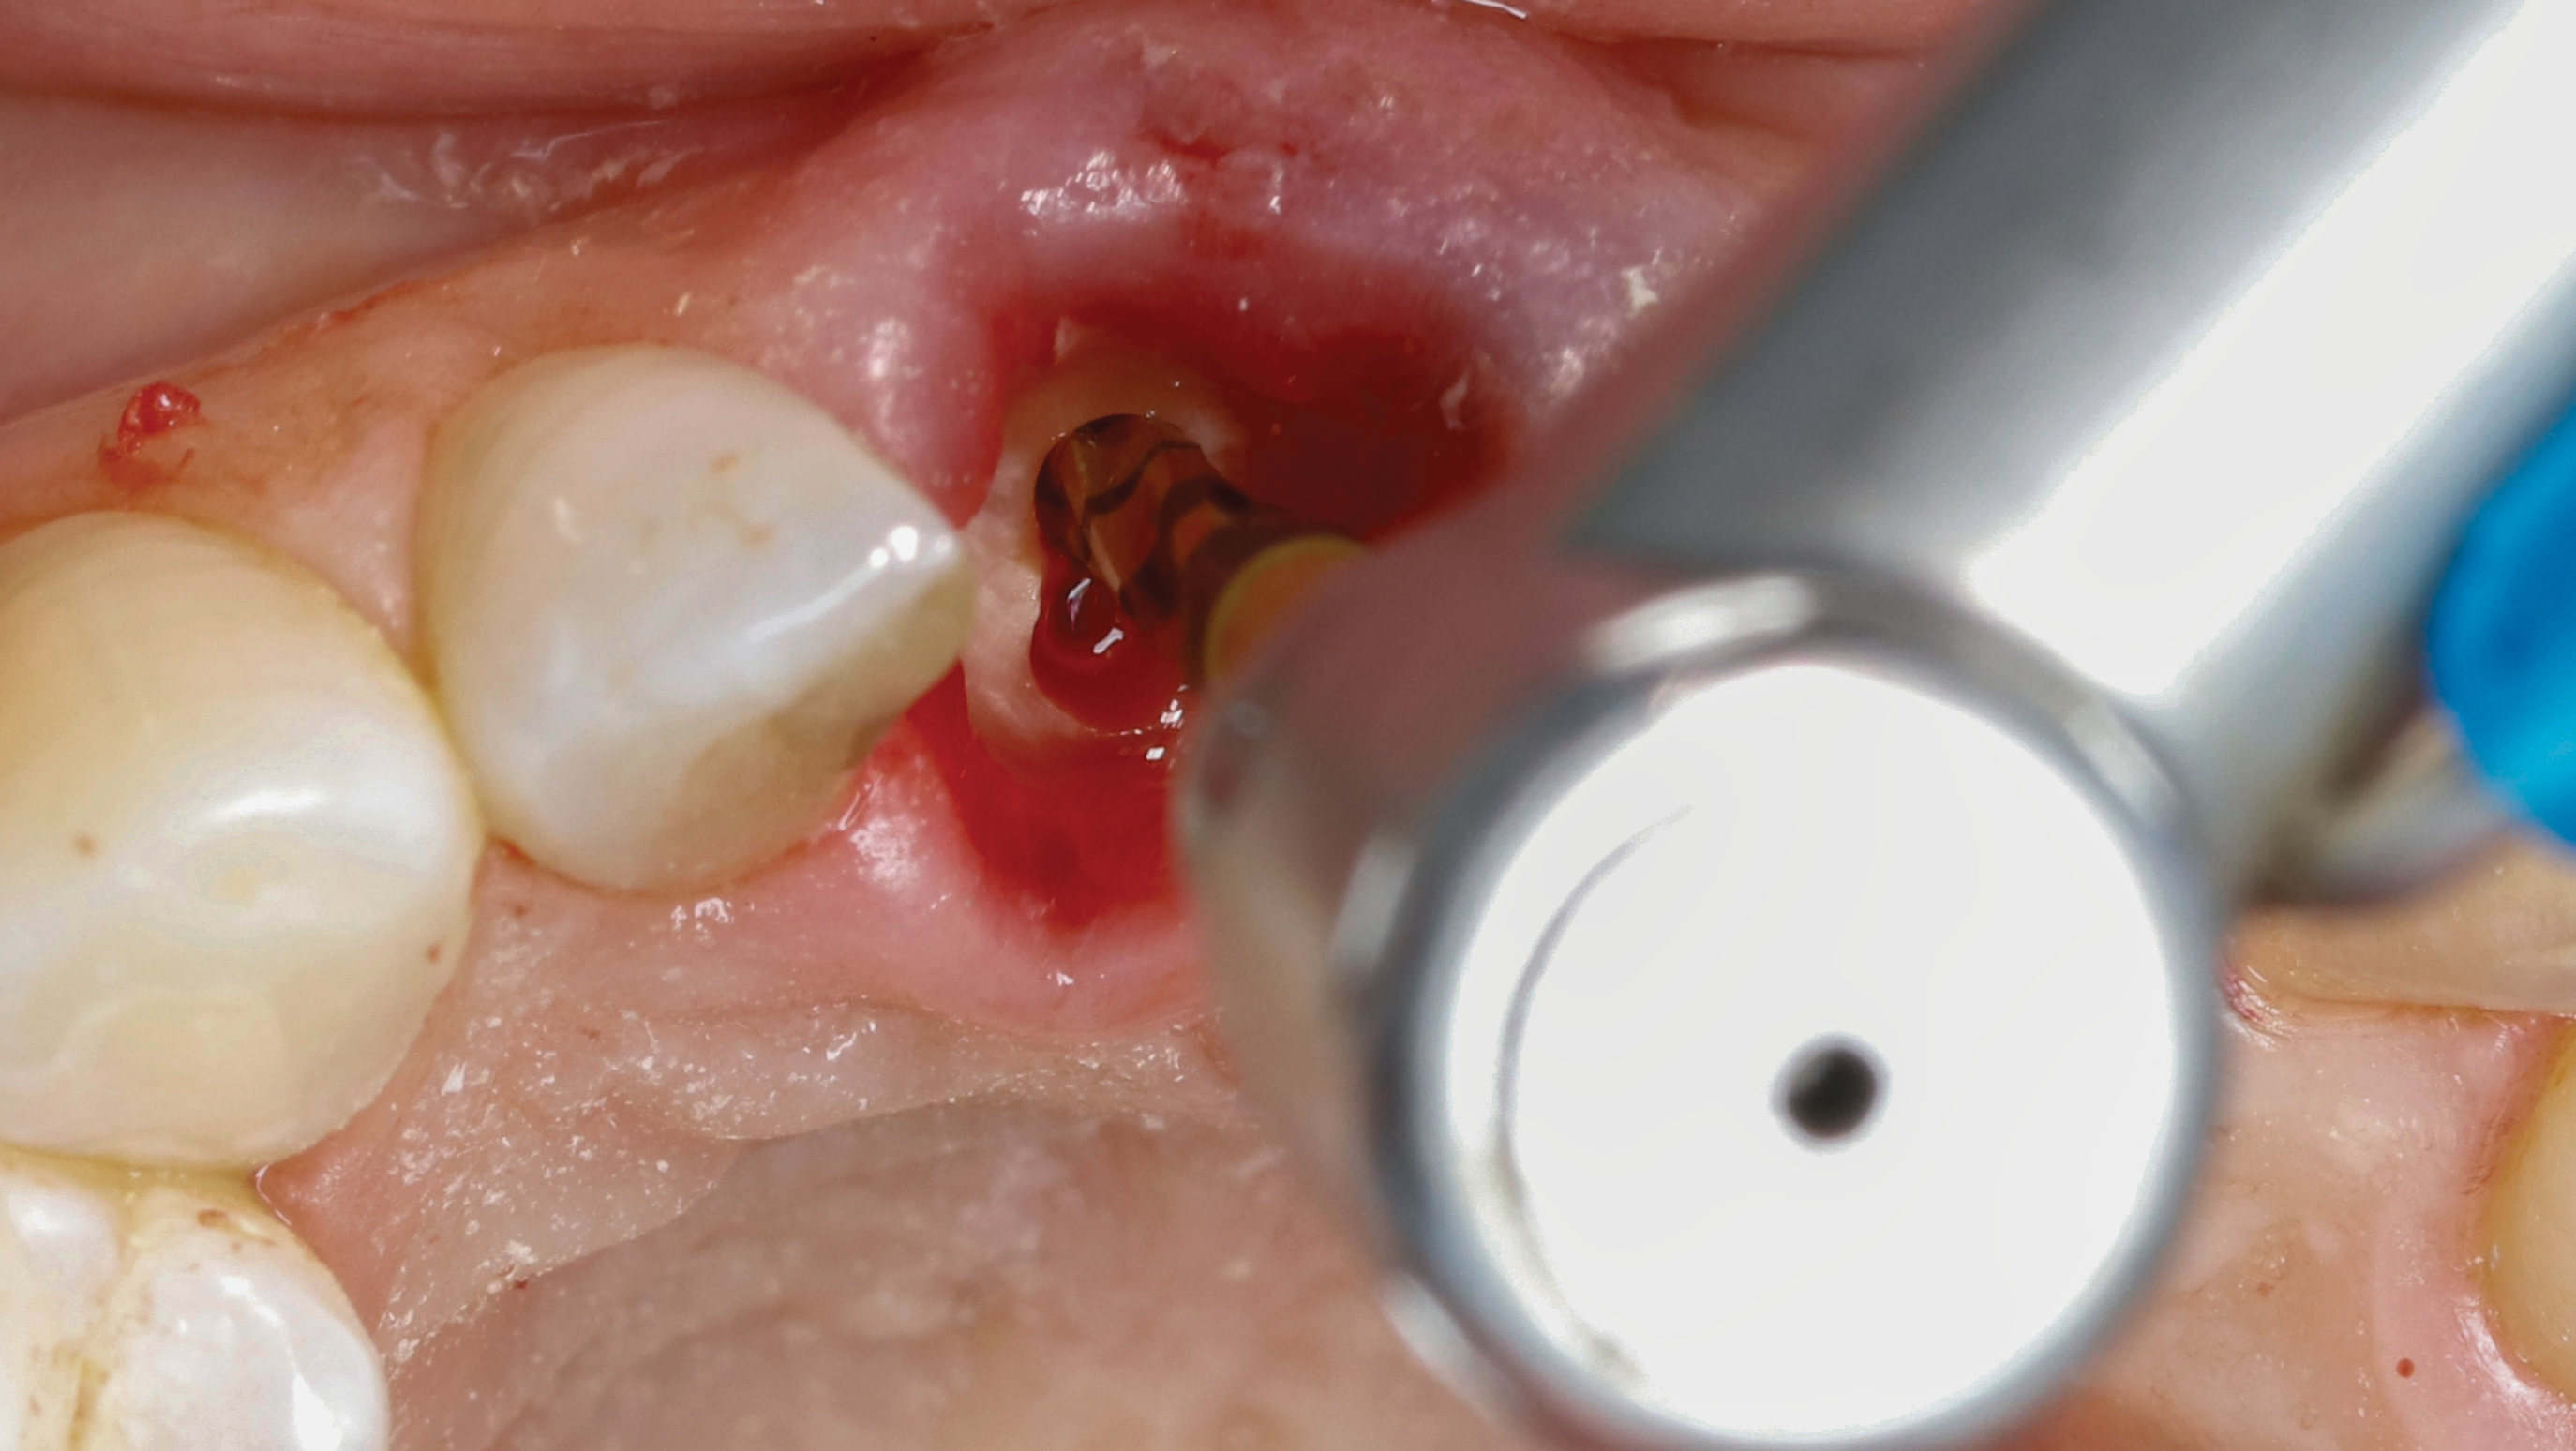

Fig 5. SPOT Step 1: After the clinical crown is removed, a high-speed diamond bur (Meisinger 801H-029) is used to hollow out the center of the tooth 2 mm to 3 mm subgingivally leaving a 1 mm rim of dentin around the root circumference.

Figure 5

Fig 9. SPOT Step 4: Densah burs VT1525 (2.0) and VT1828 (2.3) are used at 1,200 rpm with irrigation in CW mode to widen the root canal hole trajectory to provide further and complete apex removal. The same burs are then used to establish the implant osteotomy. In some cases, the two trajectory holes might eventually overlap. (Figure 11 is a composite illustration provided by the authors.)

Figure 9

Fig 10. SPOT Step 4: Densah burs VT1525 (2.0) and VT1828 (2.3) are used at 1,200 rpm with irrigation in CW mode to widen the root canal hole trajectory to provide further and complete apex removal. The same burs are then used to establish the implant osteotomy. In some cases, the two trajectory holes might eventually overlap. (Figure 11 is a composite illustration provided by the authors.)

Figure 10